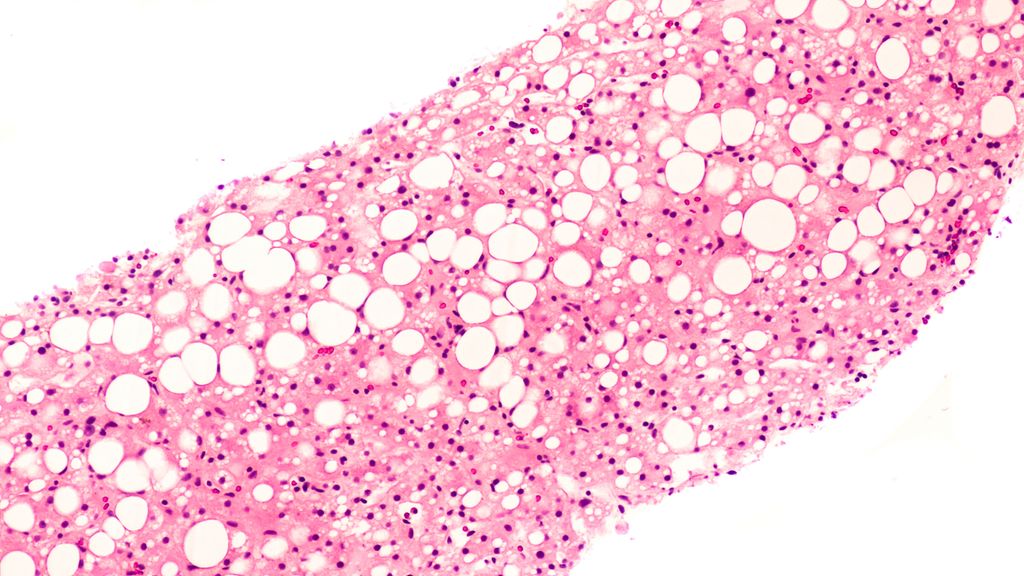

La chimiothérapie intra-artérielle constitue une extension efficace de l’éventail des traitements des tumeurs malignes hépatiques primitives et secondaires avancées. La chimiothérapie ...